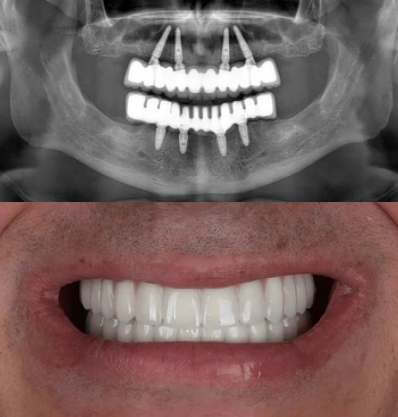

Usually, full mouth dental implant treatments use four, six or eight implants per single jaw. The increased number of implant screws provides more stability to the attached fixed bridge that replaces the patient’s teeth, though some patients can lack jawbone density for eight or six implants per jaw.

The process starts with a full dental consultation, during which dentists check the patient's oral health and talk about their specific wants and goals. Diagnostic imaging, such as panoramic X-rays, may be used at this first visit to check the health of the jawbone and structures nearby. With this information, the dentist can make a personalised treatment plan for you, discussing options such as implant systems and any necessary dental preparation.

The next stage after creating the treatment plan is to surgically place the implants. Dental doctors insert titanium screws into the jawbone using tiny incisions. For the patient's comfort, we apply anaesthesia during this process. The screws hold the new teeth in place. Once the implants are in, the bone needs to heal for a few months so that it can join with the implants, making the tooth stable and strong.

Stage 3: Attachment of permanent teeth

Total implants required for complete mouth restoration